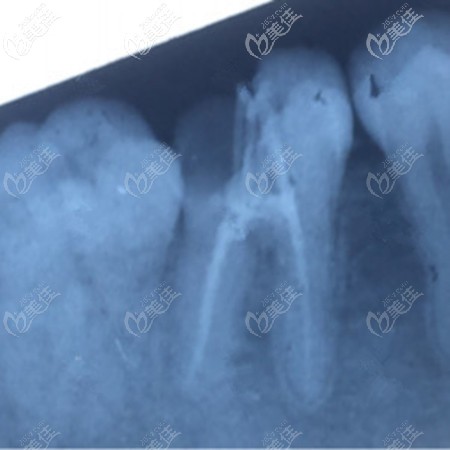

到院后,医生就先给我拍片,看看牙齿的基本情况。牙齿的状态还是不错的,牙神经没有受损,就是牙齿缺了一个口子,也不用做根管治疗,只用补牙就可以了!